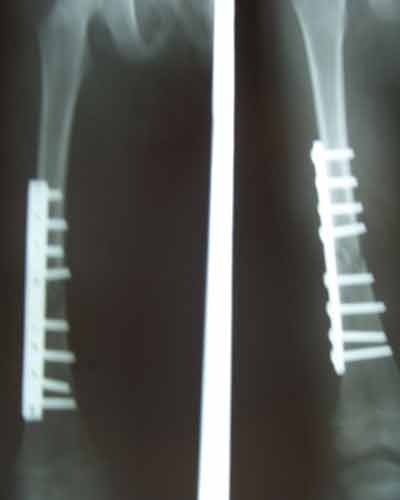

Case:8 Polytrauma

Patient having closed segmented fracture midshaft & lower 1/3 Tibia with closed fracture superior & inferior pubic rami right side with pelvis fracture following vehicular accident wastreated with intramedullary nail for fracture tibia and external fixator for fracture pelvis.

Pre-Op

Immdiate Post-op

Post-op Lateral

Ex fix with frame

Post-op 1 and half months follow-up

Post Uninon-3Months